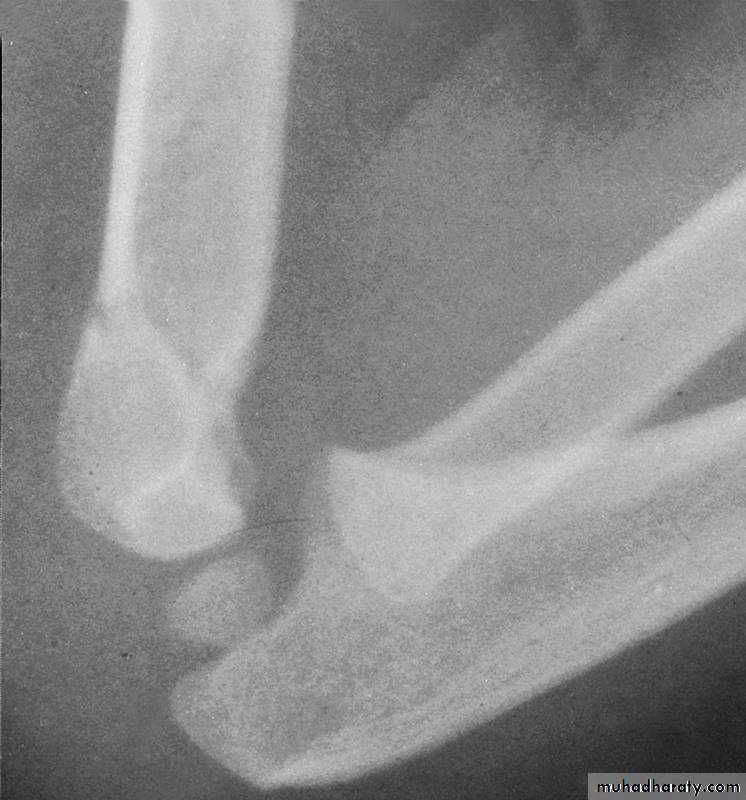

may not be adequate !!The elbow must be flexed to 120 0

Injury filmReduced at 1200

Reduction lost

at 900WARNING

Flexing to > 1200 may increase the riskof vascular problems.